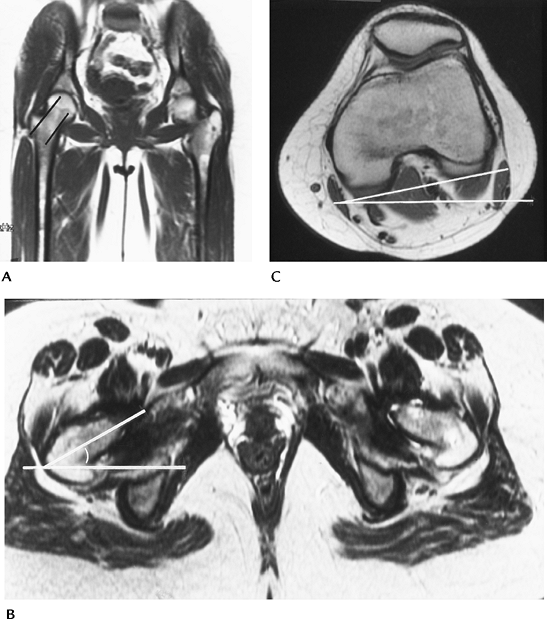

FIGURE 4-56 Femoral anteversion measurement. (A) Coronal MR image demonstrating oblique angle for axial images (lines). (B) Axial image of the hips with line through the plane of the neck and horizontal line forming the angle. (C)

Axial image of the knee. A line is drawn along the posterior condyles and the angle formed by the horizontal line. If the knee is externally rotated, as in this case, the knee angle is subtracted from the axial femoral angle. If the knee is internally rotated, the angle is added to the femoral angle to measure the degree of anteversion. |